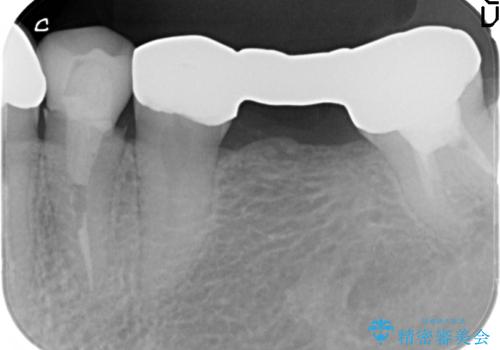

精度の高いジルコニアブリッジの製作に加え歯茎にぴったりとそわせたオベイトポンティック形態とすることで清掃性・審美性に優れたブリッジを製作します。

歯ぐきの形態にそわせ、凸型でくぼみのないオベイト型のポンティックはプラークの溜まりにくく審美性も達成できるポンティック形態です。